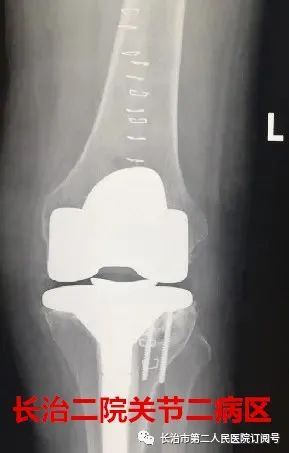

走路 在常人来看 是件多么轻松的事情 可对于李老太来说 近日,长治二院骨科关节二病区来了一位严重类风湿性关节炎患者,疾病困扰了她13年,日常行走已经很困难了。 长治二院骨科关节二病区 雷晓宇医师团队妙手回春 完美实施双膝关节置换术 随即轻松行走! 对李老太来说 走路成为了一种享受 今年69岁的李老太在13年前双膝先后出现疼痛无力的症状,但随着年龄的增长病情逐年加重,双腿关节等处都严重变形。双膝并拢时成“顺风腿”畸形,行走也变得相当困难,行各种保守治疗方案效果差,双膝疼痛行走受限,严重影响了日常生活。 图为:术前MRI及CT 图为:术后X片 据李老太的主管医生朱彦伟副主任医师介绍“重度外翻性膝行膝关节置换,由于其软组织不平衡及存在严重的骨缺损,手术难度极高,对于关节外科医师而言,绝对是充满挑战性事件! 入院后,骨科关节二病区雷晓宇医师团队术前进行仔细的手术规划,充分的术前准备,为李老太制定个性化治疗方案,对存在不同严重畸形的双膝分别行人工膝关节表面置换术。术后第二天就可以在助行器的保护下下床行走。经过精心的康复治疗,目前李老太的行走步态正常,生活质量明显提高。科室医护人员对李老太住院期间的精心治疗和护理,更是让老人及家属感受到了长治二院医护团队的专业素养和暖心服务。 对于像李老太这样的类风湿性关节炎患者,长治二院骨科关节二病区雷晓宇主任特别提醒:一旦出现疼痛、关节畸形、保守治疗无效后,应尽早行膝关节置换。 朱彦伟 关节二病区副主任医师 朱彦伟医师:周四全天门诊 电话:158 3551 0903 ■ 直通大医院丨9月18日长治二院关节外科一病区主任张鹏为您讲解《股骨头坏死的预防与诊治》 ■ 皮肤病患者的福音——又一“名医工作室”落户长治二院!!! ■ 长治二院特邀北京大学第一医院皮肤科教授陈喜雪来院指导讲学 供 稿丨朱彦伟 视 频 | 朱彦伟 编 辑丨张静晗 审 核丨雷 赫